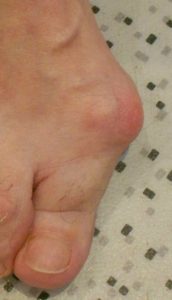

Hallux valgus is a forefoot deformation concerning the big toe (called hallux). It is deviated laterally towards the other toes and a “bump” appears on the medial side of the foot. It is commonly called “bunion”.

Bursitis

The bone protrusion at the medial aspect of the foot is in conflict with the shoe. When the conflict lasts, a red and hot “inflammatory” zone appears. Very painful at the slightest contact it’s called bursitis when filled with liquid. In the most evolved cases, the bursitis tears and a viscous content poors out. The risk of deep infection comes when skin germs take advantage of the opening to colonize the cavity.